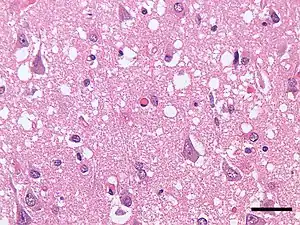

| Micrograph showing spongiform degeneration (vacuoles that appear as holes in tissue sections) in the cerebral cortex of a patient who had died of Creutzfeldt–Jakob disease. H&E stain, scale bar = 30 microns (0.03 mm). | |

Transmissible spongiform encephalopathies (TSEs) also known as prion diseases,[1] are a group of progressive, incurable, and fatal conditions that are associated with prions and affect the brain and nervous system of many animals, including humans, cattle, and sheep. According to the most widespread hypothesis, they are transmitted by prions, though some other data suggest an involvement of a Spiroplasma infection.[2] Mental and physical abilities deteriorate and many tiny holes appear in the cortex causing it to appear like a sponge when brain tissue obtained at autopsy is examined under a microscope. The disorders cause impairment of brain function, including memory changes, personality changes and problems with movement that worsen chronically.

The degenerative tissue damage caused by human prion diseases (CJD, GSS, and kuru) is characterised by four features: spongiform change (the presence of many small holes), the death of neurons, astrocytosis (abnormal increase in the number of astrocytes due to the destruction of nearby neurons), and amyloid plaque formation. These features are shared with prion diseases in animals, and the recognition of these similarities prompted the first attempts to transmit a human prion disease (kuru) to a primate in 1966, followed by CJD in 1968 and GSS in 1981. These neuropathological features have formed the basis of the histological diagnosis of human prion diseases for many years, although it was recognized that these changes are enormously variable both from case to case and within the central nervous system in individual cases.[13]

Early neuropathological reports on human prion diseases suffered from a confusion of nomenclature, in which the significance of the diagnostic feature of spongiform change was occasionally overlooked. The subsequent demonstration that human prion diseases were transmissible reinforced the importance of spongiform change as a diagnostic feature, reflected in the use of the term "spongiform encephalopathy" for this group of disorders.